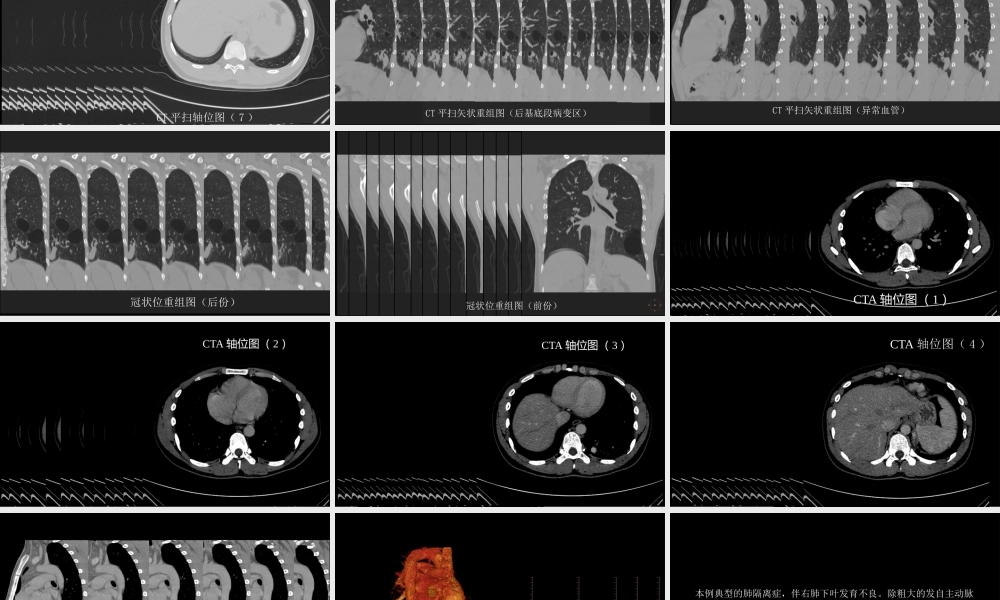

这样的肺隔离症:影像共享中国石油中心医院影像科杨景震注:请使用放映模式浏览2016年病例交流(11)男,24岁,咳嗽,咳痰。既往2年前左下肺炎,外院曾经建议做增强CT,当时未同意。此次为复查。CT平扫轴位图(纵隔窗)CT平扫轴位图(1)CT平扫轴位图(2)CT平扫轴位图(3)CT平扫轴位图(4)CT平扫轴位图(5)CT平扫轴位图(6)CT平扫轴位图(7)CT平扫矢状重组图(后基底段病变区)CT平扫矢状重组图(异常血管)冠状位重组图(后份)冠状位重组图(前份)CTA轴位图(1)CTA轴位图(2)CTA轴位图(3)CTA轴位图(4)肺部CTA斜矢状重组图CTA容积重建图本例典型的肺隔离症,伴右肺下叶发育不良。除粗大的发自主动脉的粗大异常血管外,还可见增粗的引流静脉,于三维重建图显示最直观。鉴别诊断“体循环血管供应肺”,本病不存在肺部的病变(隔离肺的囊性或块状灶),多伴有病变区肺动脉发育差。男,37岁。咳血,其他无特殊症状。增强扫描:左下肺GGO、体循环血管增多男,34岁。无明显临床症状。看到主动脉发出的异常动脉血管供应肺,不全都是肺隔离症;虽然是属于一种发育变异,但是否看作是“定时炸弹”——大咳血危险因素?复习文献中的经典病例后,你将会重视这种情况K.Tokunaga,etalECR2015EducationalExhibitPulmonaryvascularanomaliesinadult;apictorialreview女,62岁。大咳血。胸片:心脏、气管及纵隔右移位,右肺体积缩小,右侧肺门及肺部血管细小,右肺中野侵润。与左侧对比,右侧没有正常的肺纹理结构、形态!增强胸部CT及3D-CTA证实右肺动脉主干缺如。肺窗显示右肺体积缩小伴磨玻璃影以及双侧肺气肿。CTA显示源自支气管动脉、肋间动脉、胸廓内动脉、膈下动脉以及冠脉诸多侧枝血管供应右肺。右侧肺静脉狭窄。单侧肺动脉缺如UnilateralAbsenceofaPulmonaryArtery(UAPA)CTA显示源自支气管动脉、肋间动脉、胸廓内动脉、膈下动脉以及冠脉诸多侧枝血管供应右肺。肺通气灌注显像:右侧全肺V/Q(通气/血流)不匹配正常通气显像正常灌注显像该例UPAP一个值得注意的问题:本例的右肺看似含气的肺组织,但是它却是多余的(没有肺应有的气体交换功能);由于供应右肺的体循环血管破裂,而导致大咳血、最终死亡。对此或类似的体循环异常供血,尤其畸形血管较粗大者,一旦确诊,是否应尽早予以手术治疗?END